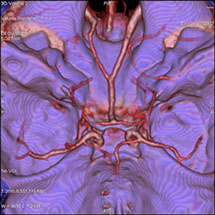

On peut faire ressortir le contraste de certains tissus, en particulier des vaisseaux sanguins, en injectant un produit dit "de contraste" (contenant de l'iode) qui a la propriété de fortement absorber les rayons X et donc de rendre très visibles les tissus où ce produit est présent (qui apparaissent alors hyperdenses, c'est à dire plus "blancs" sur l'image).

Grâce aux scanners multidétecteurs (ou multi-barrettes) à acquisition spiralée, on obtient une exploration très précise d'un large volume du corps humain pour un temps d'acquisition de quelques dizaines de secondes.

• Les pathologies vasculaires (dilatations d’artères : anévrysmes, les rétrécissements : sténoses).